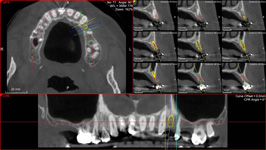

NewTom Implant Planing

Jedná se o plánovací program, který využívá dat získaných při vyšetření pomocí přístroje New Tom. Tento program umožňuje tříprostorovou počítačovou simulaci při plánování pozic implantátů.

Součástí programu je i databáze, ve které mohou být uloženy všechny typy implantátů od všech výrobců, včetně jejich délek, průměrů i tvarů.

Lékař si vytvoří všechny typy zobrazení potřebných pro naplánování – tedy 2D snímky (panoramatický), příčné řezy i 3D model.

Vidí zde i důležité anatomické útvary – čelistní dutinu, průběh nervu atd. Po proměření množství kosti – šířky i výšky vybere z databáze vhodný typ implantátu a umístí ho do požadované lokality.

Ihned vidí jeho pozici ve všech 3 rovinách a na všech snímcích i 3D modelu. Může upravovat podle potřeby jeho pozici, sklon atd.

Všechny vybrané a správně umístěné simulované implantáty se ukládají do „počítačové karty“ pacienta s jejich pozicí, délkou, průměrem, typem i sklonem.

Lékař i pacient tedy ještě před vlastní operací vidí, jak by mělo ošetření probíhat a vypadat.